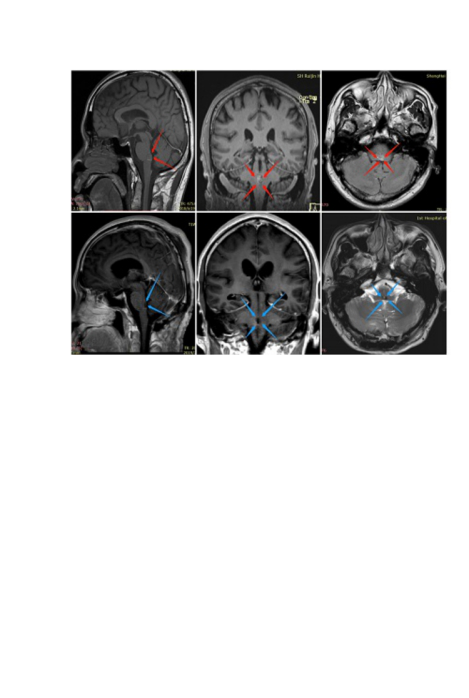

巴特朗菲教授脑干海绵状血管瘤经典案例